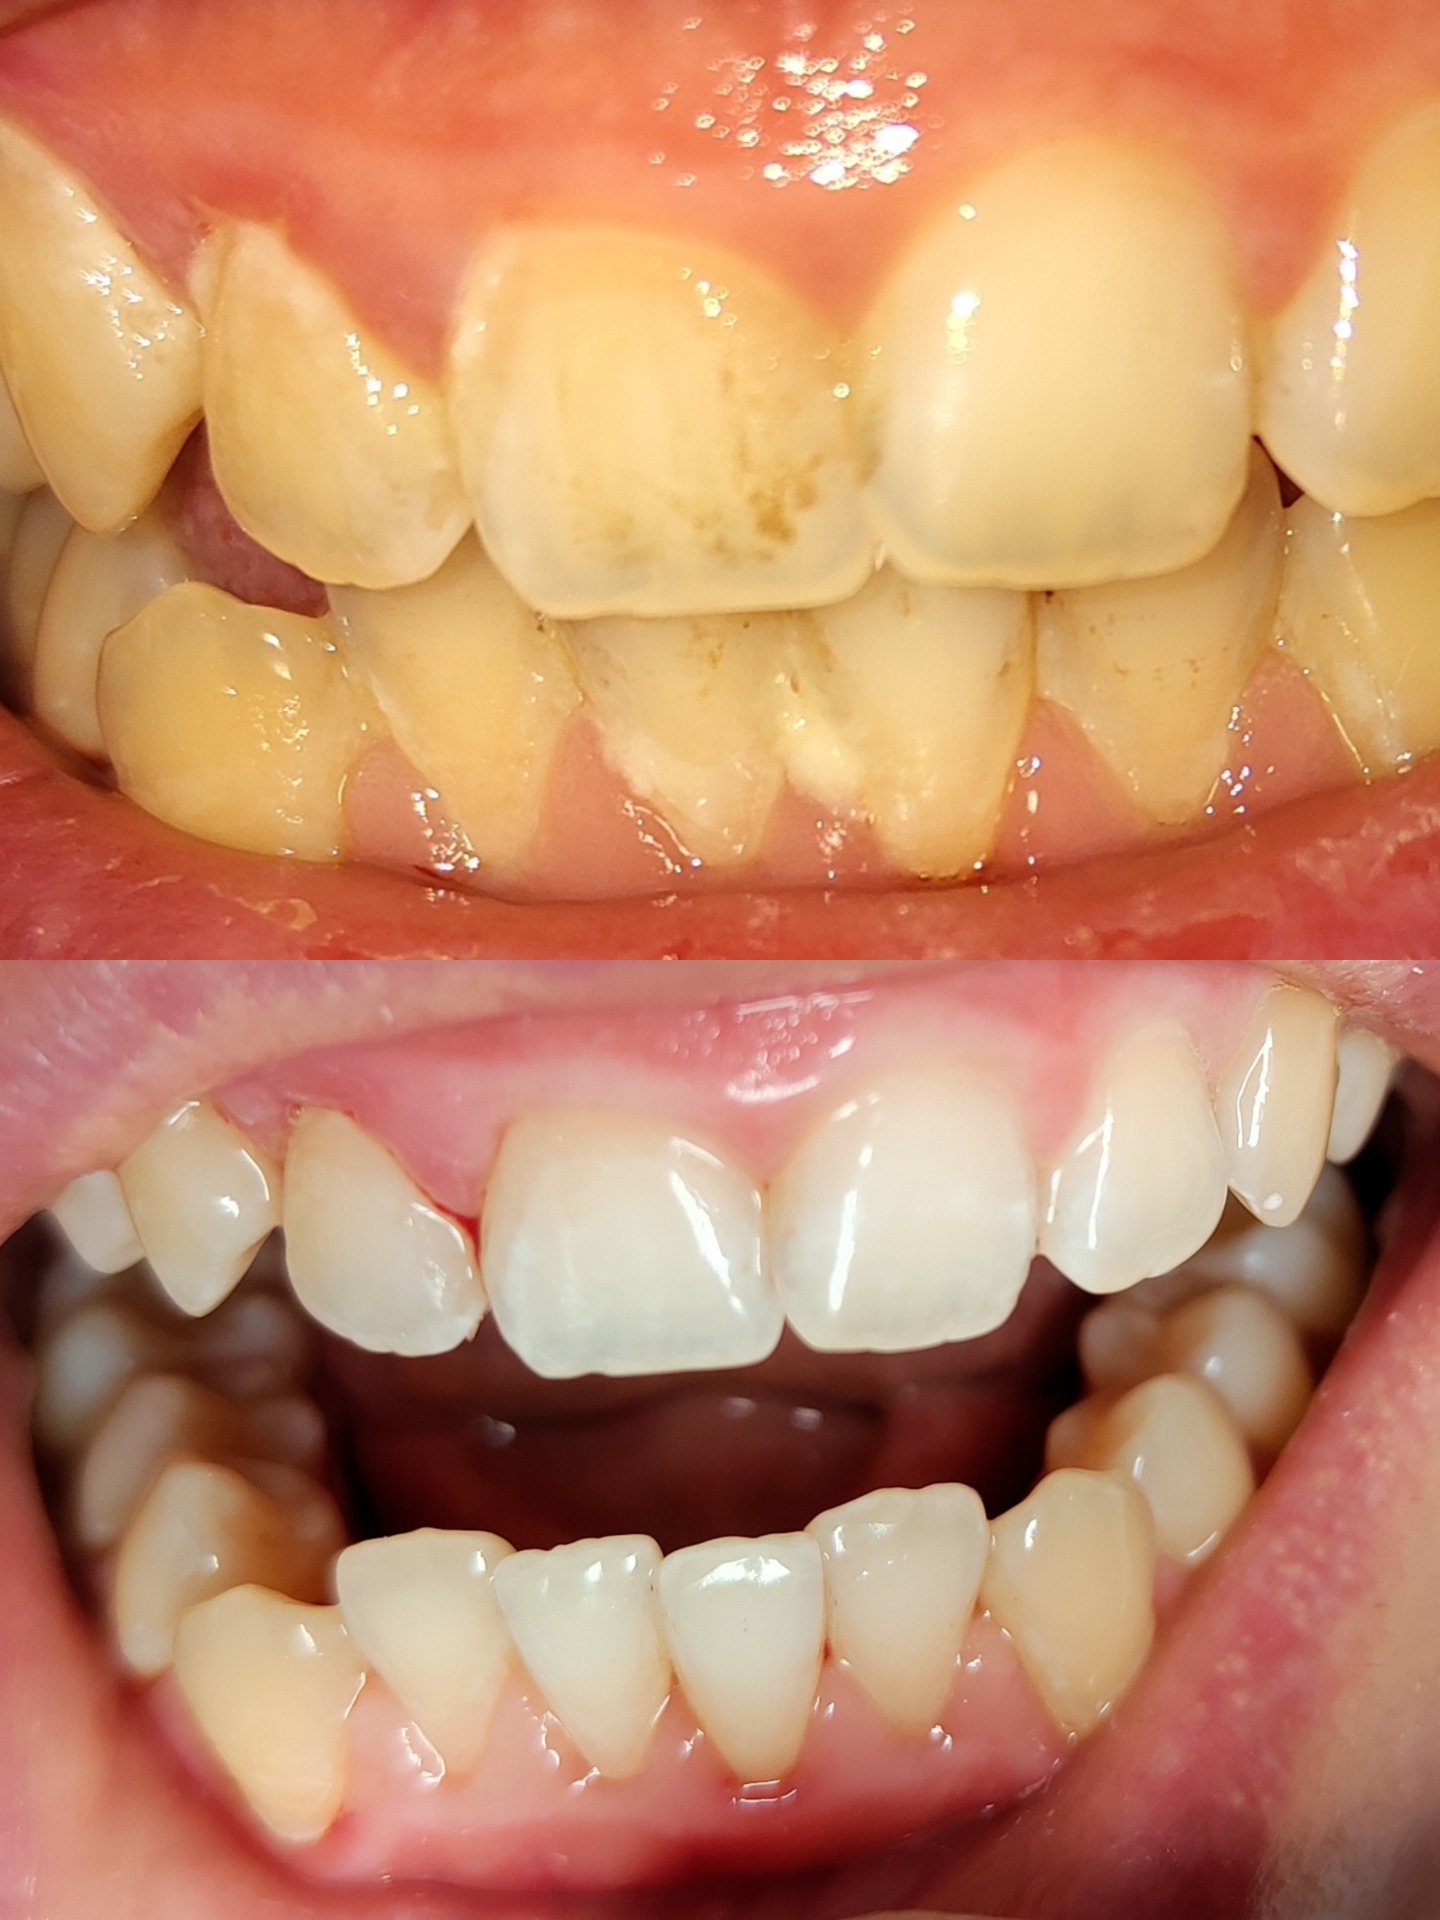

Pravidelným čištěním odstraňujete doma lepkavý film na povrchu zubu – plak. Neodstraněný plak např. v těžko dostupných nebo při nedostatečné péči však časem mineralizuje a tvoří se tvrdý zubní kámen. Plak a zubní kámen obsahují bakterie, jejichž produkty způsobují zánět dásně. Ten se pak projevuje krvácením, zápachem z úst apod. Dlouhodobý zánět už ohrožuje závěsný aparát zubu a může vést ke ztrátě zubů. Bakterie v místě zánětu jsou pak podkladem i pro vznik zubního kazu.

- motivace a instruktáž jsou nezbytnou součástí péče o chrup. Návštěva profesionální dentální hygieny je prvním krokem, stejně zásadní je ale váš přístup a úroveň domácí péče mezi naplánovanými návštěvami. Klademe důraz na vzájemnou komunikaci, nejen na techniku čištění. Fotodokumentace intraorální kamerou nám pomáhá porovnat jednotlivé snímky a zhodnotit úroveň dentální hygieny v čase. Dozvíte se souvislosti, proč a jak čistit, změříme mezizubní prostory, doporučím vám pomůcky přímo na míru, probereme související oblast zdravého stravování.

Intervaly návštěv jsou stanoveny individuálně po vstupním vyšetření. Při nevyhovující hygieně tzn. velkém nánosu zubního kamene postupujeme step-by-step. Na vstupní návštěvě očistíme zuby "z nejhoršího" nad dásní a po zlepšení domácí péče a ústupu zánětu dočistíme i pod dásní. Při velkém zánětu dásně více krvácí a hlubšímu ošetření tak brání nepřehledný terén i vyšší citlivost při ošetření.